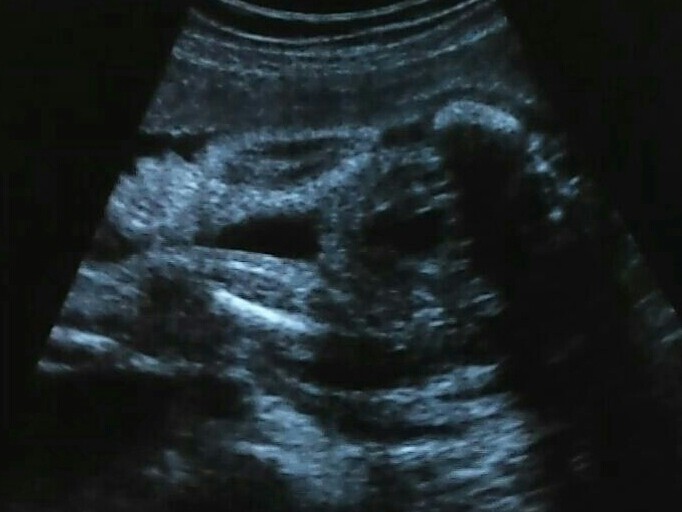

@joshi haha kochana ilez emocji! [emoji2] Jak dla mnie to Lenka tam sie chowa